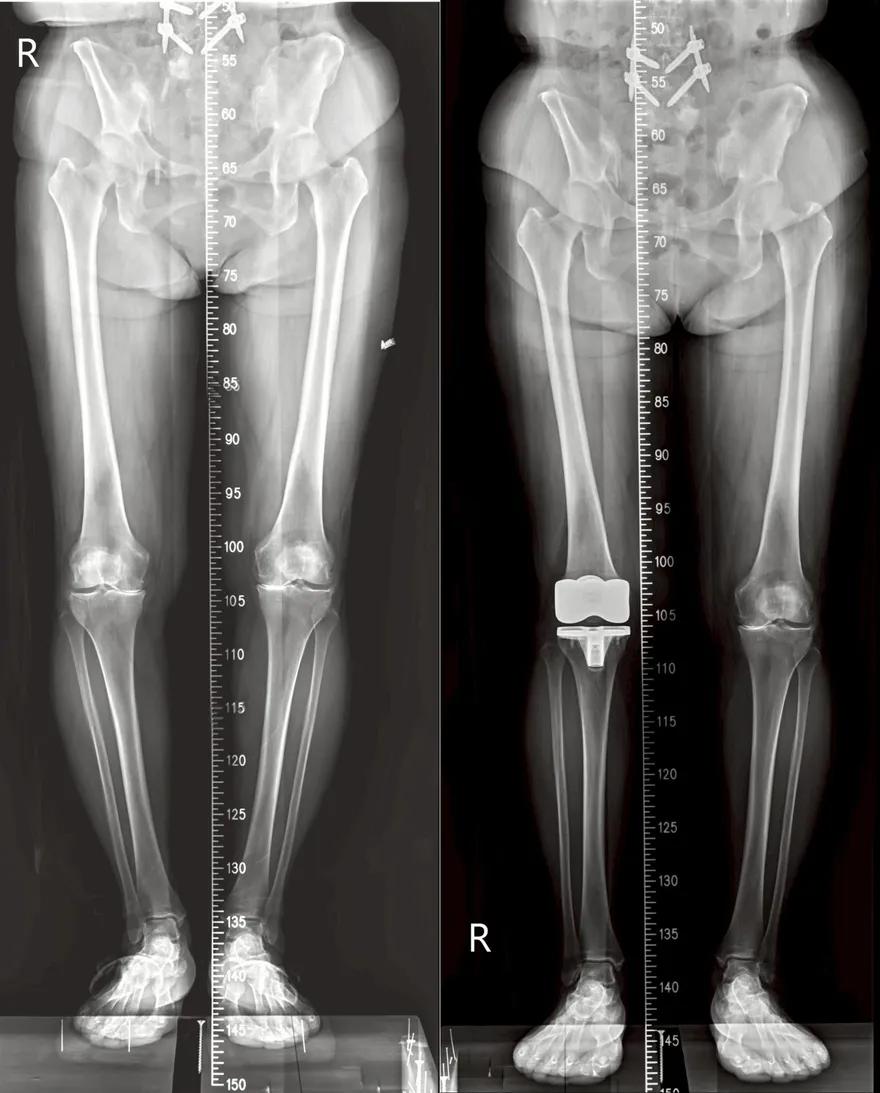

全人工膝關節置換手術

人工膝關節